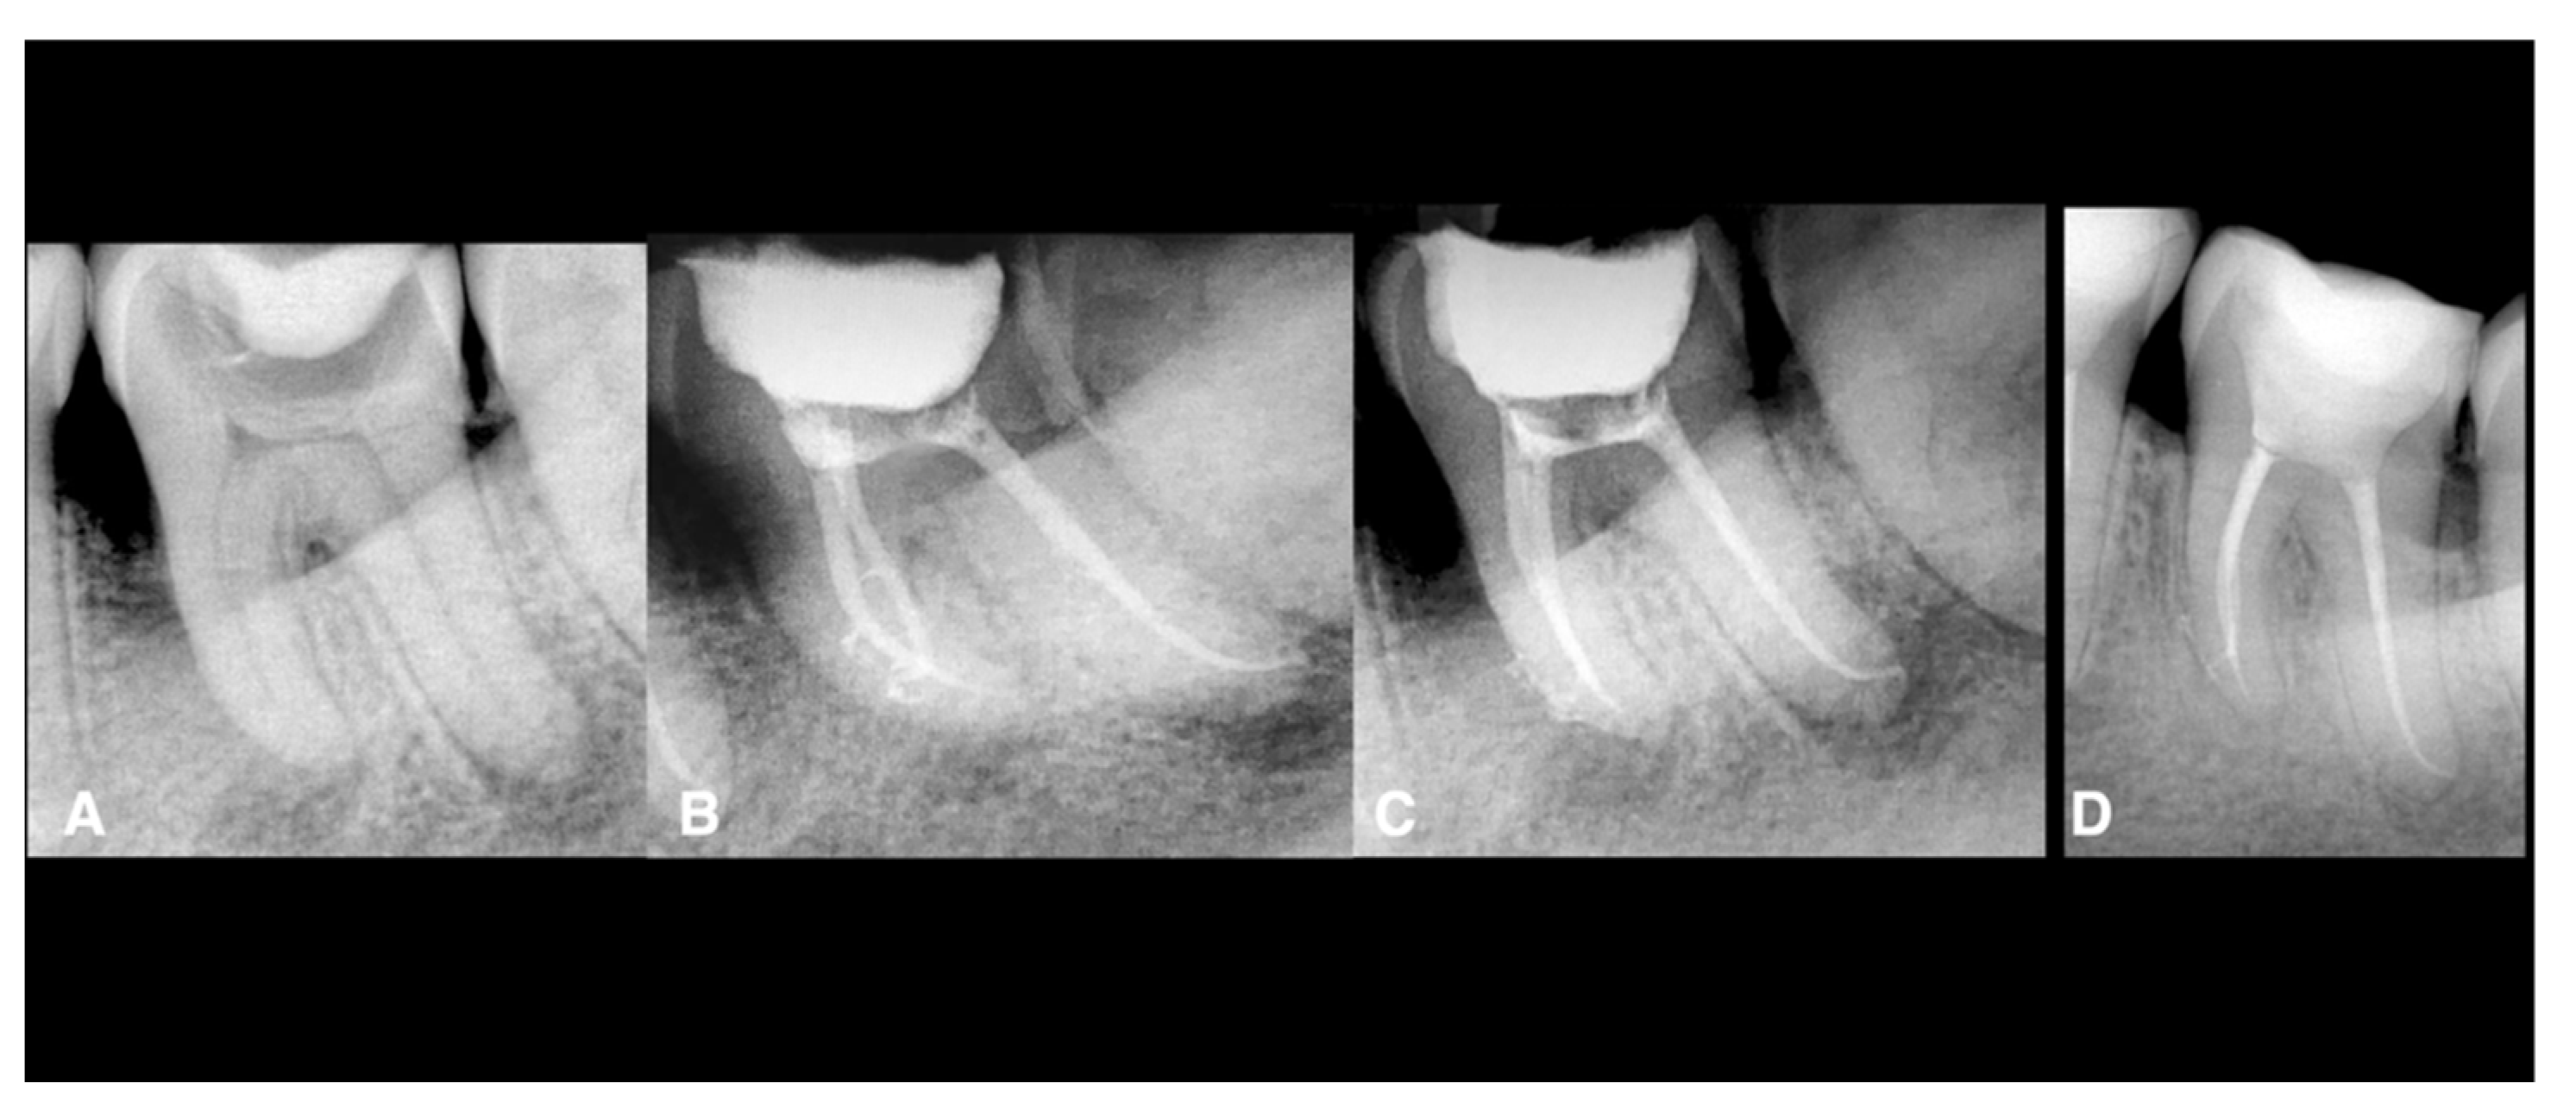

The four failed teeth were two maxillary premolars and two mandibular molars (these teeth did not have sealer extrusion). One maxillary premolar failed because of a vertical root fracture (Figure 1 and Figure 2) (Appendix A).

Figure 1.

Endodontic treatment of a second mandibular left molar. The tooth was necrotically associated with periapical lesions. The treatment was done using conservative shaping and the 3D cleaning procedure, as mentioned in the Materials and Methods. (A) Preoperative X-ray, (B) postoperative X-ray, (C) postoperative X-ray with different angulation, (D) 2-year follow-up showing healing.